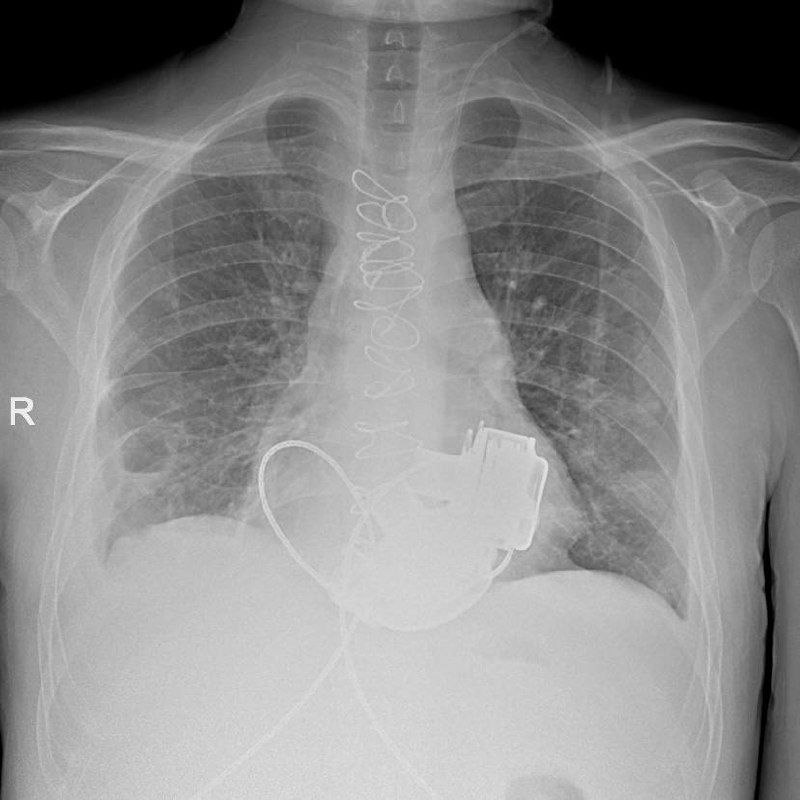

В Мариинской больнице Санкт-Петербурга готовят к выписке уникального пациента, который теперь живёт без пульса. В конце ноября ему впервые в Российской Федерации имплантировали сразу два искусственных желудочка сердца — левый и правый. 19 января его навестил председатель комитета по здравоохранению Андрей Сарана, рассказали в комздраве.

36-летний Антон поступил в стационар со сложными диагнозами — кардиомиопатией и терминальной сердечной недостаточностью. В силу осложнений (тромбоэмболии легочной артерии, инфаркт-пневмонии и других) пересадка сердца была невозможной. Главный врач больницы Игорь Реутский предложил провести имплантацию искусственных желудочков.

«Обычно пациенту вживляют одно такое устройство, но в случае Антона этого было недостаточно — нужно было сразу два прибора», — отметили в пресс-релизе.

Операцию провела бригада высококвалифицированных хирургов под управлением главного внештатного специалиста по сердечно-сосудистой хирургии комитета по здравоохранению Петербурга, академика РАН Геннадия Хубулавы.

«Операция продолжалась около четырёх часов, — отметил Геннадий Хубулава. — Для наших специалистов самым сложным было синхронизировать работу двух искусственных желудочков сердца, но с этой задачей мы успешно справились. Это доказывает высокий уровень развития кардиохирургии в нашем городе».

Антон уже готов к выписке и научился жить с двумя приборами в теле. Он выразил надежду, что вернётся в Мариинскую больницу для получения донорского сердца. Имплантация искусственных желудочков — «мостик» к трансплантации сердца, поскольку даёт пациенту возможность дожить до спасительной операции.